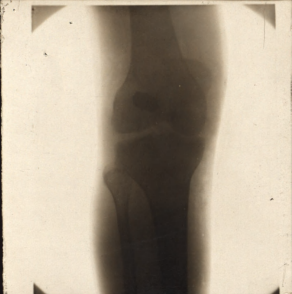

He was taken to a field hospital on 9 March and an operation was undertaken and x-rays were also taken, which has survived in the archive. I don’t know what I’m looking at here to be honest, but on 13 March it was decided that Robert needed to be returned to a hospital in England.